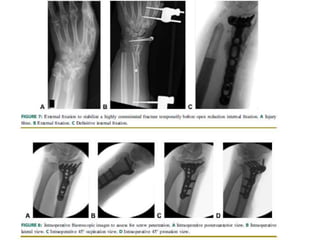

AO Surgery

Fijación externa combinada con percutanea

Reducción fijación externa combinada con

reducción abierta ,síntesis con agujas de Kirschner

Reducción fijación externacombinada con reducción abierta ,síntesis con agujas de Kirschner